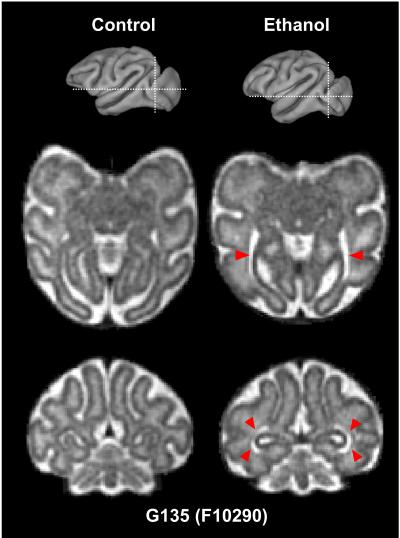

A study in monkeys finds that exposure to alcohol early in gestation affects the development of brain regions involved in motor control. Early intervention for infants suffering from fetal alcohol syndrome can reduce long-term cognitive and behavioral impacts. Recent advances in motion correction have improved the quality and resolution of 3D MRI of the fetal brain. Using in utero MRI, Xiaojie Wang and colleagues found that exposure to alcohol in the first trimester affects the development of brain regions involved in motor control in rhesus macaques. The authors examined a group of 28 female macaques. Fourteen of the macaques consumed 1.5 g of alcohol per kilogram of body weight per day. At three time-points during gestation, the authors used in utero MRI to image the fetal brains, immediately followed by electrophysiological assays of brain activity. Total brain volumes of ethanol-exposed and control fetuses did not differ. In the human equivalent of the third trimester, however, both the cerebellum and brain stem regions in the ethanol-exposed fetuses were smaller, and motor-related white matter maturation was altered, compared with controls. Electrophysiological recordings suggested that the differences are functionally significant. According to the authors, noninvasive in utero MRI may be sufficiently sensitive to be developed as a diagnostic tool for fetal alcohol syndrome as early as the third trimester.

ARTICLE #19-19048: "In utero MRI identifies consequences of early-gestation alcohol drinking on fetal brain development in rhesus macaques," by Xiaojie Wang et al.